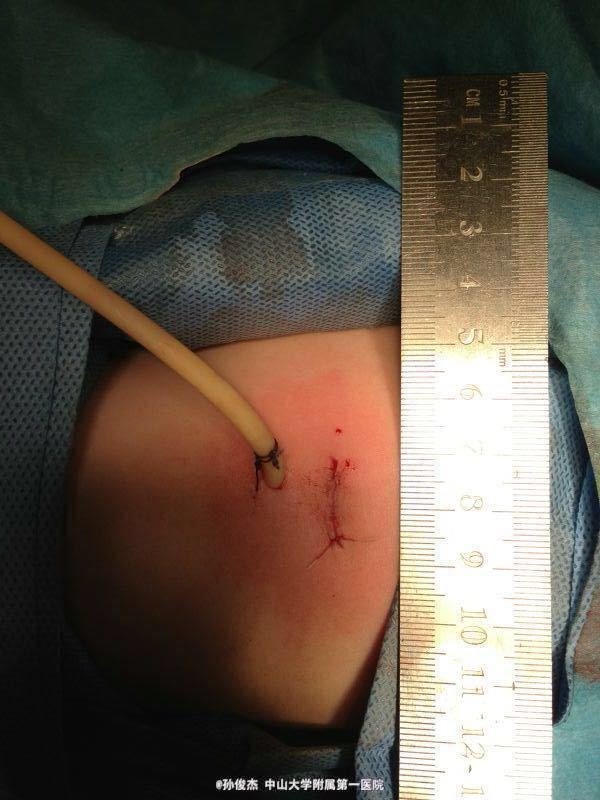

诊断明确:左肾盂输尿管连接处狭窄、左肾积水 在全麻下行离断式肾盂输尿管成形术。本人的手术方式特点是:开放,腰部切口仅1.5cm,不切断肌肉而采用钝性牵开,不穿破腹膜,完全不进腹腔,放大镜下6/0单股薇乔线吻合,根据情况放置或不放置引流。手术基本在1小时至1小时20分钟内完成。 术前无需肠道准备或留置胃管。术后当天麻醉清醒后即可进食,次日即可拔除引流管,可恢复自主活动。